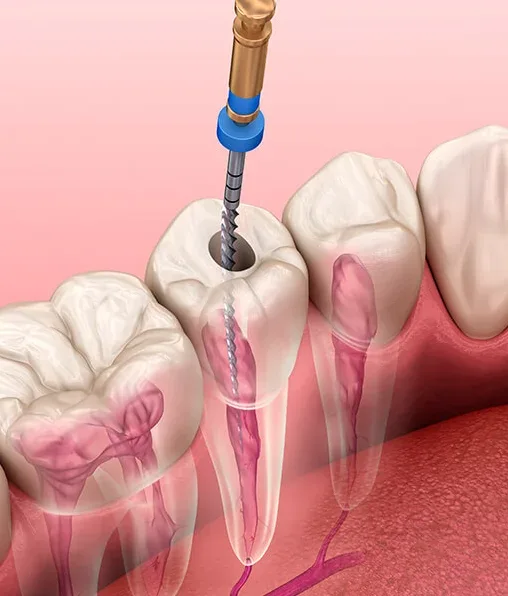

Uma unidade focada nessa especialidade oferece procedimentos de qualidade superior. Isso ocorre devido à prática constante do profissional em lidar com anatomias complexas e casos que exigem rigor técnico:

Limpeza profunda e desinfecção minuciosa dos canais radiculares;

Vedação interna realizada com materiais biocompatíveis de excelência;

Aplicação de métodos que visam a eliminação total de focos infecciosos.

Além disso, o uso de recursos atuais promove maior segurança nos processos. Equipamentos modernos auxiliam na realização de diagnósticos ágeis, fundamentando intervenções que respeitam a integridade dos tecidos bucais do paciente.

O especialista sabe como conduzir o tratamento de canal de maneira suave, desmistificando o receio comum a esse tipo de sessão. O foco é salvar a estrutura original do dente, protegendo a harmonia e a mastigação.